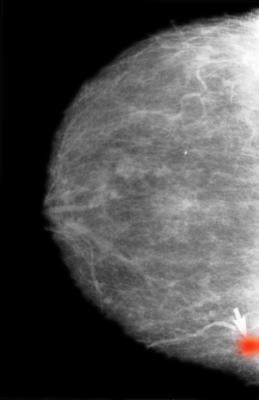

Getty Images